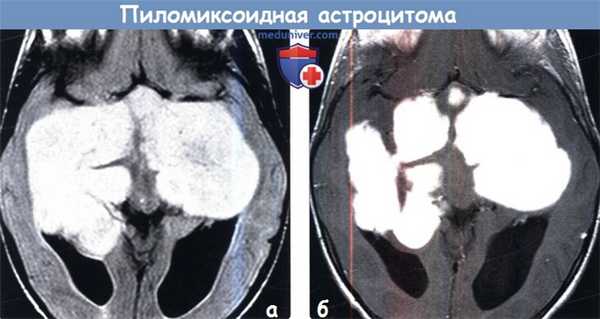

(а) МРТ, FLAIR, аксиальный срез: у трехлетнего ребенка определяется крупное супраселлярное объемное образование в форме буквы «Н», прорастающее базальные ганглии и медиальные части височных долей. Опухоль достаточно хорошо визуализируется, несмотря на размеры. Признаки перифокального отека отсутствуют.

(б) МРТ, постконтрастное Т1-ВИ, аксиальный срез: у того же пациента отмечается интенсивное однородное контрастное усиление опухоли.

• Супраселлярное объемное образование в форме буквы «Н» может являться ПмА